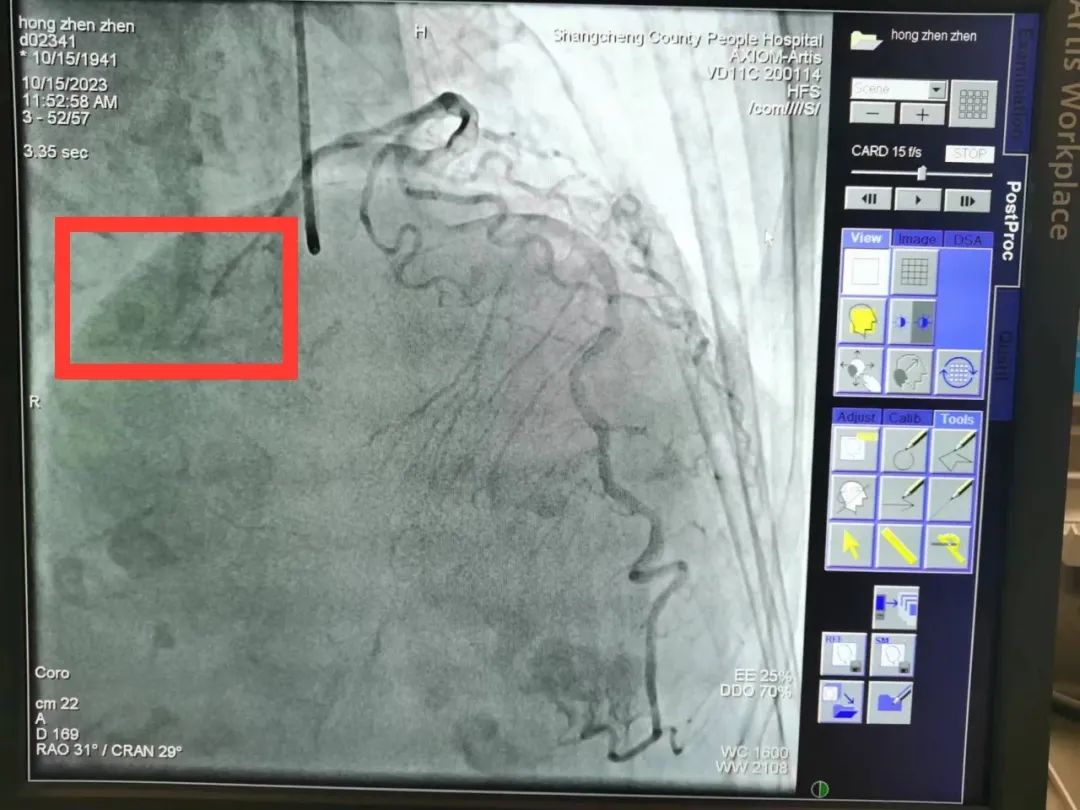

回旋支未见明显狭窄,远端可见慢血流